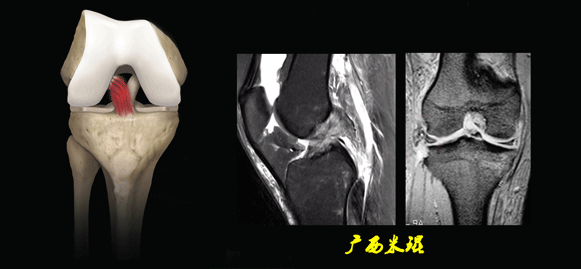

(六)ACL最常见的撕裂部位

韧带实质部>韧带股骨髁附着部>韧带胫骨附着部。

(七)ACL损伤直接征象

1)ACL本身的形态和信号异常:

5)撕脱骨折:

一般为ACL胫骨附着部的撕脱。

韧带完整,信号多正常。

6)假瘤:

韧带损伤后断端较整齐,残端组织增生并被滑膜包裹呈“瘤状”,如果突出于前方为“独眼征”。

多见于韧带股骨附着部撕裂及部分撕裂。